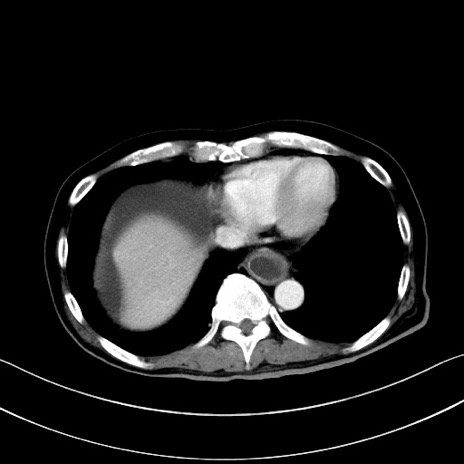

冠状断像

【症例】60歳代男性

【主訴】嘔吐

【現病歴】胃癌にて胃全摘後。食思不振が悪化し、夜中に嘔吐することがある。

【既往歴】胃癌、胃全摘、脾摘、胆摘後

【データ】WBC 5900、CRP 10.56